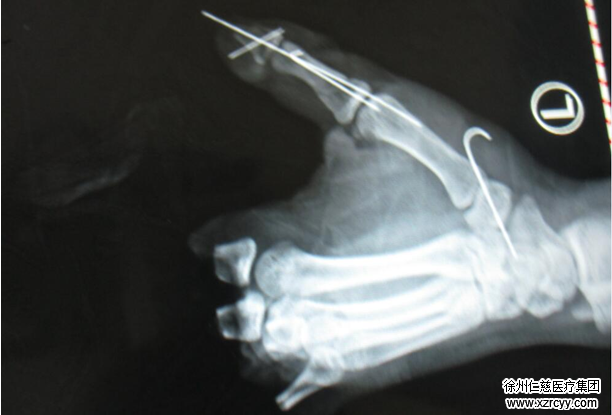

betway在线登陆手足显微外科四病区的吴尧医生介绍,“少年的左手伤的太重了,断指已经被炸没了,根本找不到了”郑大伟主任补充“双手与右足被炸伤出血,左手2-5指离断,右环指中节指骨折。”

简单的问诊后,小飞被紧急送往手术室。因包扎伤创面污染较严重,无法行一期再造,此次手术主要进行右手骨折复位内固定及清创标记断裂的血管神经肌腱断端,为二期手指再造进行相应的准备。待创面情况稳定进行皮瓣修复创面,创面愈合后予以脚趾移植手指再造。术后患者的左手功能将恢复原来的七八分。